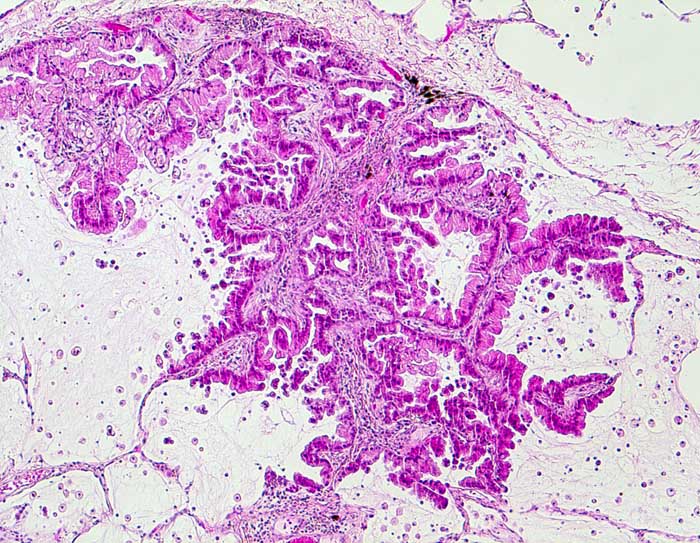

Bronchioloalveoläres Karzinom der Lunge

Das Bronchioloalveoläre Karzinom stellt eine Variante des Adenokarzinoms dar. Die Tumorzellen wachsen per Definition auf dem intakten Alveolargerüst, ohne das Stroma zu infiltrieren. Nicht selten zeigen Ausläufer gewöhnlicher Adenokarzinome ein bronchioloalveoläres Wachstumsmuster. Bei diesen Tumoren handelt es sich jedoch nicht um echte bronchioloalveoläre Karzinome. Da eine Invasion zytologisch nicht ausgeschlossen werden kann, ist die zytologische Diagnose eines bronchioloalveolären Karzinoms nicht eindeutig möglich. Die Karzinomzellen schilfern in kleinen Gruppen oder dreidimensionalen Verbänden in die Alveolarlichtungen ab. Multiple kleine papilliforme Zellverbände, die mit Creolakörperchen verwechselt werden können, sind typisch. Im Sputum erscheinen die Tumorzellen kleiner als die der üblichen Adenokarzinome. Die Kerne liegen exzentrisch, sind rund und glatt begrenzt, das Chromatin ist blass. Kernkerben und Pseudoinklusionen sind möglich, Nukleolen sind unauffällig. Das reichlich vorhandene Zytoplasma färbt sich blass eosinophil bis blass zyanophil. Beim muzinösen Subtyp ist es unterschiedlich vakuolisiert. Aufgrund der geringen Kernatypien ist die Unterscheidung von einer Becherzellhyperplasie bisweilen schwierig. Pseudoepitheliale Verbände aktivierter Makrophagen und hyperplastische Alveolarzellen, wie sie bei Lungeninfarkten oder Lungenfibrosen vorkommen verschwinden im Gegensatz zum ähnlich aussehenden bronchioloalveolären Karzinom in wiederholten Sputumkontrollen.

Der erste Fall zeigt ein muzinöses, der zweite Fall ein nicht muzinöses bronchioloalveoläres Karzinom.